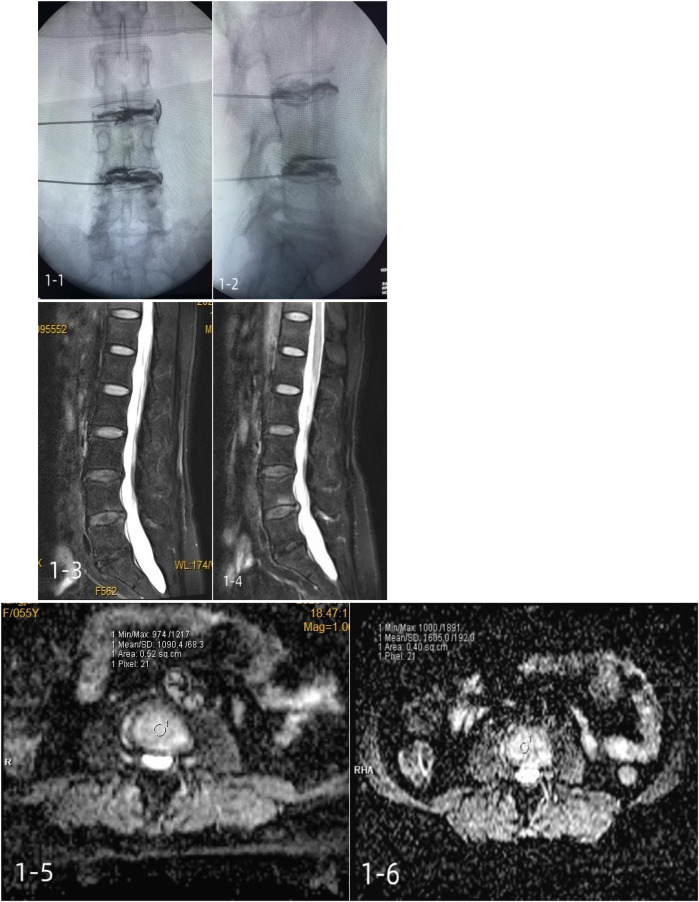

Methods: A total of 40 patients with discogenic low back pain were randomly divided into two groups, with 20 patients in group A receiving platelet-rich plasma injections and 20 patients in group B receiving methylene blue injections. Visual analog scale (VAS) scores, Japanese Orthopaedic Association (JOA) scores, Pfirrmann grades, and MRI apparent diffusion coefficients (ADCs) were recorded in both groups before the injections and 6 months after the injections.

Results: Compared with group B, the postoperative VAS score of group A was significantly decreased, while the JOA score and ADC score were significantly increased (P < 0.05). There was no significant difference in Pfirrmann grade between the two groups after surgery (P > 0.05). In group A, the Pfirrmann grade after surgery was lower than before surgery (P < 0.05), and the ADC score was higher than before surgery (P < 0.05). There was no significant difference in Pfirrmann grade for the patients in group B before and after surgery (P > 0.05), and their ADC score was lower than that before surgery (P < 0.05).